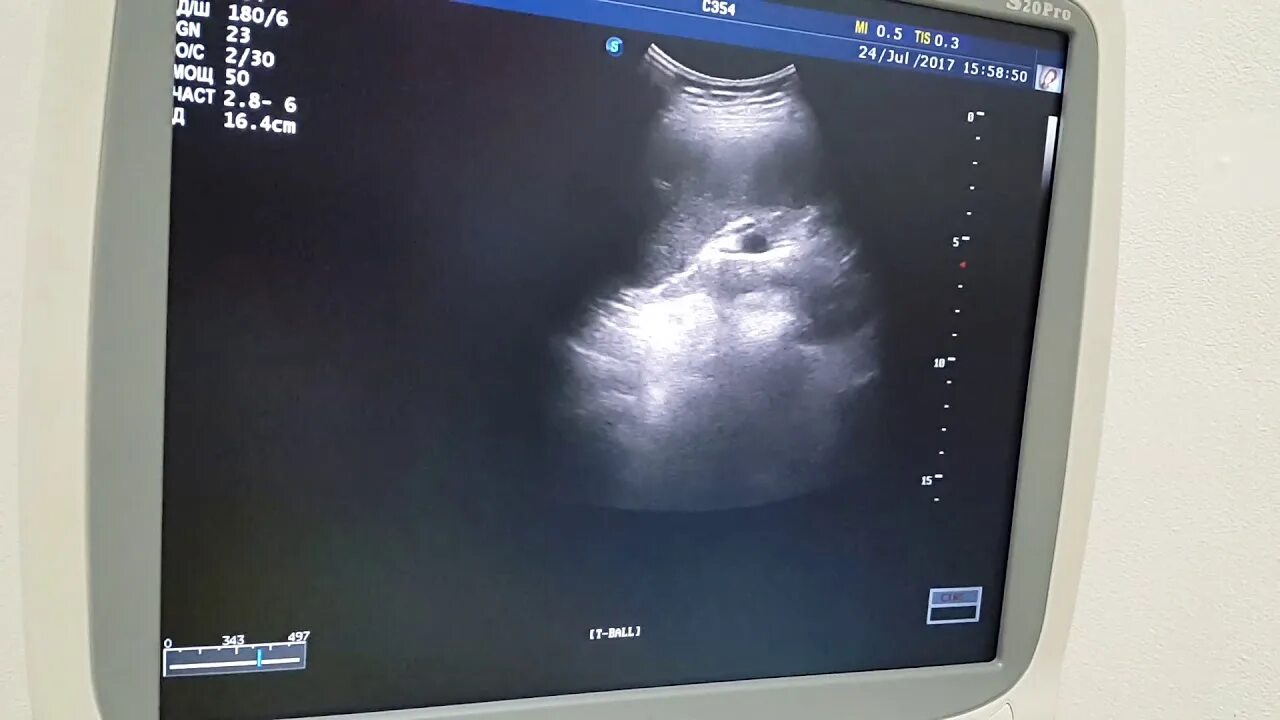

Кальцинат узи